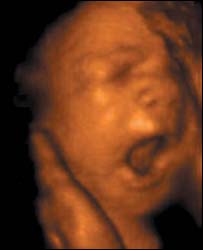

बच्चा 12वें हफ़्ते में अंगड़ाई लेने लगता है

नए अल्ट्रॉसाउंड स्कैन ने जो तस्वीरें ली हैं उसमें 12 सप्ताह के भ्रूण को गर्भाशय में 'चलते' हुए देखा जा सकता है.

इतना ही नहीं नए स्कैन से यह भी देखा जा सकता है कि माँ के पेट में बच्चा किस तरह जम्हाई लेता है और किस तरह अपनी आँखें मलता है.

लंदन के क्रिएट हेल्थ क्लिनिक में प्रोफ़ेसर स्टूअर्ट कैम्पबेल ने यह नई स्कैन मशीन विकसित की है और इसमें आम स्कैन मशीनों की तुलना में ज़्यादा स्पष्ट तस्वीरें देखीं जा सकती हैं.

त्रि-आयामी चित्र

प्रोफ़ेसर कैम्पबेल ने जो मशीन तैयार की है वह न केवल त्रि-आयामी तस्वीर लेती है बल्कि उसे उसी समय रिकॉर्ड भी कर लेती है.

उन्होंने जो तस्वीरें खीचीं हैं उनमें देखा जा सकता है :

- 12 सप्ताह का भ्रूण अंगड़ाई लेता है और हाथ पैर चलाने लगता है, हालांकि तब तक माँ को बच्चे की गतिविधियों का पता नहीं चलता है.

- 18 सप्ताह का भ्रूण अपनी आँखें खोलने लगता है, अब तक डॉक्टर मानते थे कि भ्रूण जब तक 26 सप्ताह का नहीं हो जाता वह अपनी आँखें नहीं खोलता.

-26 सप्ताह का बच्चा किसी बच्चे की ही तरह हरकतें करने लगता है, मसलन वह मुस्कुराता है, रोता है, हिचकियाँ लेता है, खुजलाता है और अंगूठा चूसता है.